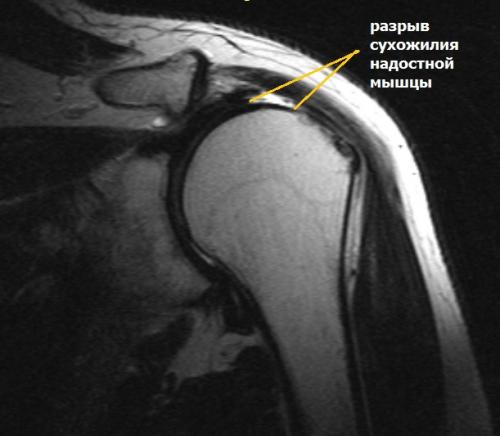

Ушиб плеча не могу поднять руку. Повреждения вращательной манжеты

К повреждению сухожилий вращательной манжеты могут приводить несколько причин:

- дегенеративные изменения;

- сужение пространства между акромионом и головкой плечевой кости;

- травма;

- хроническая травматизация.

Дегенеративные изменения связаны с нарушением кровообращения сухожилий вращательной манжеты, процессом старения и износом тканей, а также с качественными изменениями коллагеновых волокон в составе сухожилий.

Сужение пространства между акромионом и головкой плечевой кости (импинджмент-синдром) возникает на фоне особого строения акромиального отростка или после получения травмы. Сухожилие надостной мышцы, проходящее в данном пространстве, попадает как бы в тиски и постепенно сдавливается.

Характерными травмами являются падение на область плечевого сустава или на вытянутую вперед руку, резкое поднятие тяжести, резкое отведение руки в сторону.

Частые микротравмы области плечевого сустава возникают у людей тяжелого физического труда и бросающих атлетов. К типичным профессиям можно отнести и тех, у кого работа связана с длительным положением руки на уровне 900и выше. Это, к примеру, парикмахеры, стоматологи, электрики, плотники, маляры.

Симптомы разрыва вращательной манжеты.

Небольшие разрывы или частичные повреждения могут проходить бессимптомно. Но чаще всего ведущим признаком является боль. При факте травмы боль возникает резко, а при повторяющихся нагрузках она усиливается постепенно и со временем нарастает. Наибольшая интенсивность боли определяется при отведении руки по дуге от 600до 1200. Периодически боль усиливается ночью и приводит к нарушению сна.

Во время осмотра можно выявить снижение силы мышц травмированной конечности. Болевые ощущения ограничивают объем движений в плечевом суставе и приводят к развитию контрактуры (тугоподвижности).